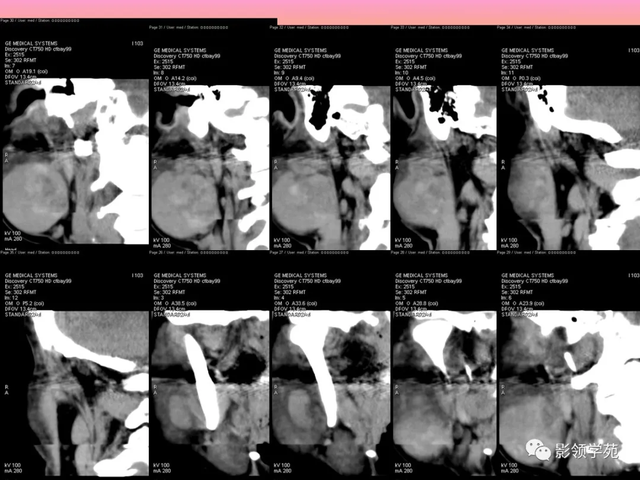

病例3:男性,68岁,因“发现右耳垂下肿物30余年”:

病理:腺淋巴瘤

病例4:男性,81岁,因发现右耳下肿物10年余,举行 性增大2年: